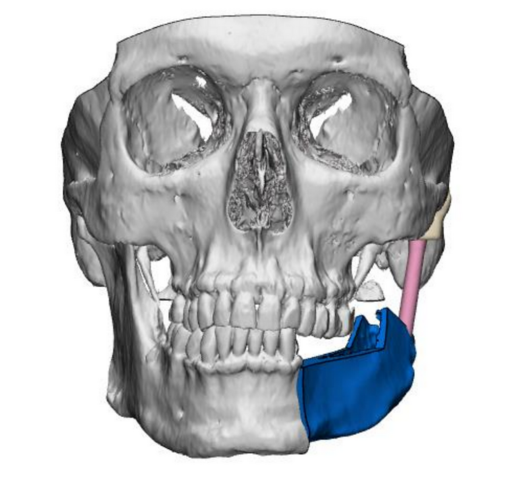

Jednym z najbardziej skomplikowanych zabiegów z przeprowadzonych w Klinice była rekonstrukcja stawu skroniowo-żuchwowego z wykorzystaniem materiału alloplastycznego, wykonanego w technologii druku 3D. W tym przypadku dodatkowo zastosowano płat biodrowy kostno-mięśniowy, pobrany za pomocą szablonu przygotowanego indywidualnie dla pacjenta. To rozwiązanie otwiera nowe możliwości leczenia pacjentów z nowotworami w obrębie części twarzowej czaszki, znacząco poprawiając ich jakość życia.